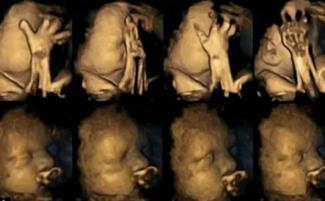

Na titulky po celom svete sa dostali silné zábery nenarodených detí v maternici. Tie sa zvíjajú a robia grimasy, keď si ich mamy zapaľujú cigaretu. Dôsledky týchto snímkov dokazujú viac než len ohrozenie, ktoré spôsobuje fajčenie počas tehotenstva – dokazujú tiež nepopierateľnú realitu života v maternici.

Vďaka použitiu pohyblivého snímku 4D ultrazvuku, doktorka Nadja Reisslandová sledovala deti v maternici v 24., 28., 32. a 36. týždni. Zistila, že vždy keď si mamička zapáli cigaretu, dieťatko sebou šklblo.

Štúdia „monitorovala 20 matiek, ktoré navštevovali Univerzitnú nemocincu Jamesa Cooka v Middlesbrough; štyri z nich fajčili v priemere 14 cigariet denne“. A tieto snímky sú mrazivé.